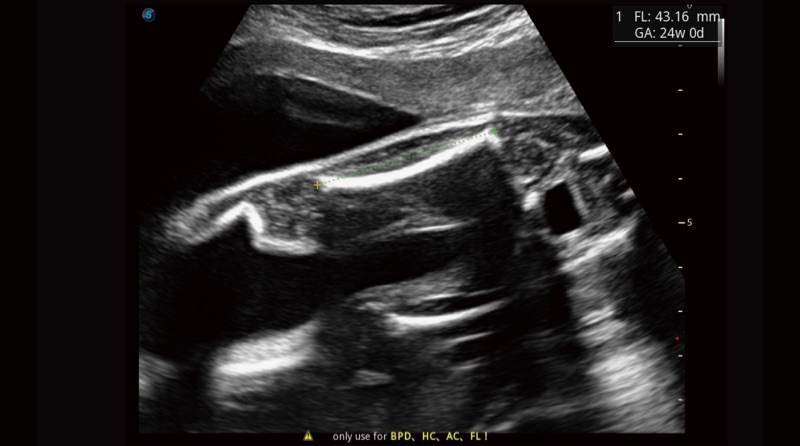

S-Fetus

„S-Fetus“, paremtas gilaus mokymosi algoritmu, pagrįstu dideliu duomenų kiekiu, yra puikus vieno langelio sprendimas automatiniam standartinių plokštumų įsigijimui ir matavimui. Vos vienu spustelėjimu gaunami įprasti vaisiaus biometrijos rezultatai, pasižymintys dideliu išmone, tikslumu ir efektyvumu, siekiant precedento neturinčio paprastumo darbo metu.